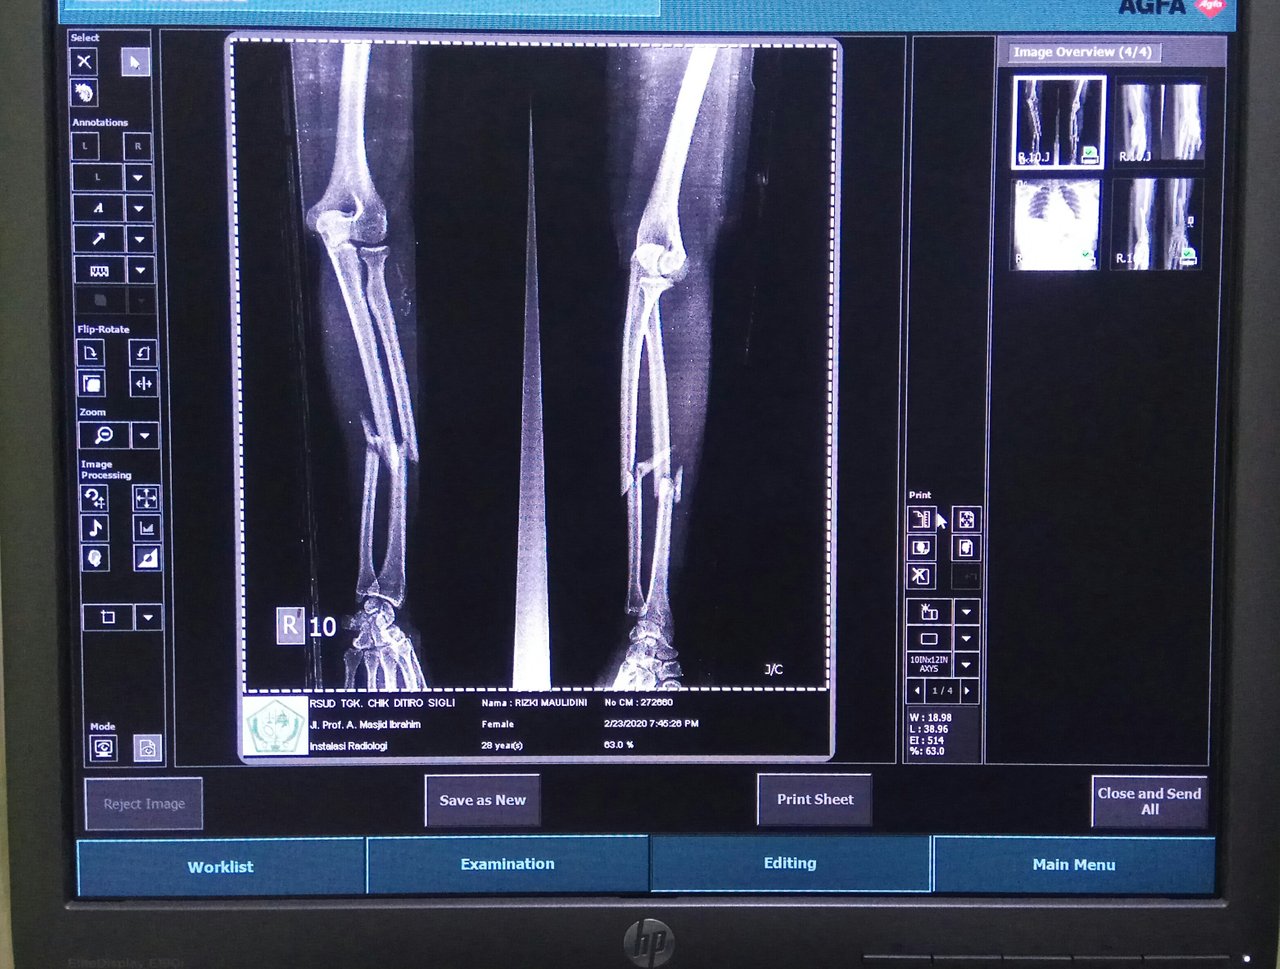

The woman was diagnosed with fractures in the right arm and left arm. Also experiencing dislocation on both wrists. It also experienced pain in the chest. So the doctor in charge of the emergency department requested a radiological examination of these organs.

The first is that I examine my left arm and left wrist. Then I did a check on his right arm and right wrist. After that I asked the patient's family to take off the patient's clothes and use the replacement clothes that we had provided. Because I have to do an inspection on the chest. In addition to clothes, also must be removed BH. Also the necklace must be removed. This is so that later in the image produced after radiological examination, there is no shadow of these objects.

After completing radiological examination, the resulting image showed that this woman had fractures in both arms and also had dislocations on both wrists. While in the chest and ribs there is no visible abnormality.